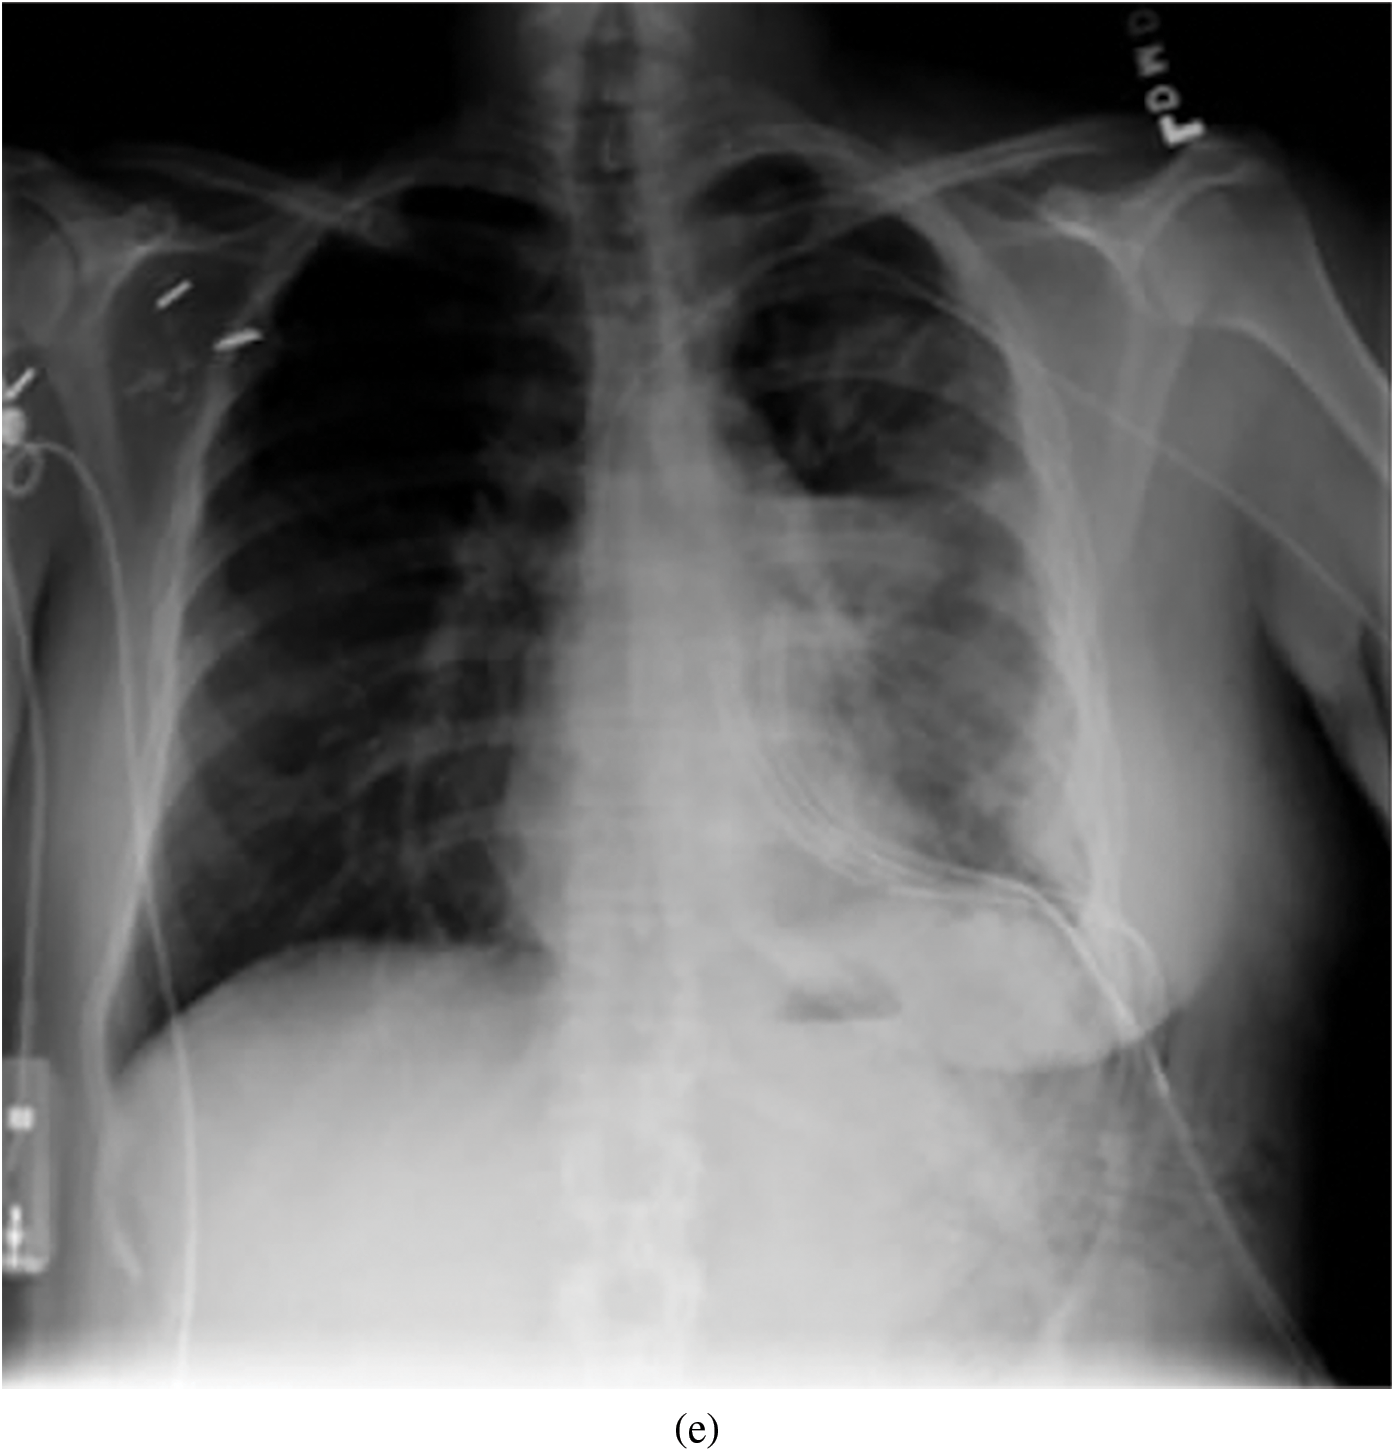

Representative images belonging to the normal, COVID-19, LO, and VP groups are shown in Figs. 2–5, along with their corresponding histograms. The images clearly depict variability in pixel intensities, particularly in and around the lung regions. The visibility of the rib cages is very obvious in the case of the normal and COVID-19 images as shown in Figs. 2a, 2b, 3a and 3b respectively compared to the LO and VP images in Fig. 4a, 4b, 5a and 5b. The visibility of lungs in COVID-19 patients is unclear. The histograms represent different perspectives, with varying distribution of intensities across the four categories, particularly COVID-19, indicating a large presence of high pixel intensities.

Figure 3: Representative image and its corresponding histogram depicting the distribution of pixel intensities of a COVID-19 image

The input images subjected to filtering using the Sato filter are shown in Fig. 7. Among the four images depicted, it can be observed that the normal, LO, and VP images shown in Figs. 7a, 7c and 7d show the bony structures.

In contrast, the same structures were not prominent in the case of COVID-19 (Fig. 8b). This analysis further helped the objective of this study to explore the texture and vessel-like structures in CXR images. The confusion matrices computed for 4-class, 3-class and 2-class classifier models using RF and DT are shown in Figs. 8–10, respectively. In all the cases, the best accuracy measure was associated with normal images for all three pathologies. The graphical comparison of the performance Measures of 3-class and 4-class models is observed in Figs. 11 and 12, respectively.